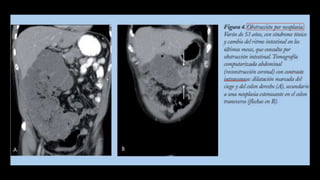

Asas dilatadas, colapsadas

o de calibre normal

Engrosamiento con

hipocaptacion de la pared

Ingurgitacion de vasos

mesentéricos

Obstrucción en asa cerrada

Colapso intestinal

Gas en sistema portal o

neumoperitoneo